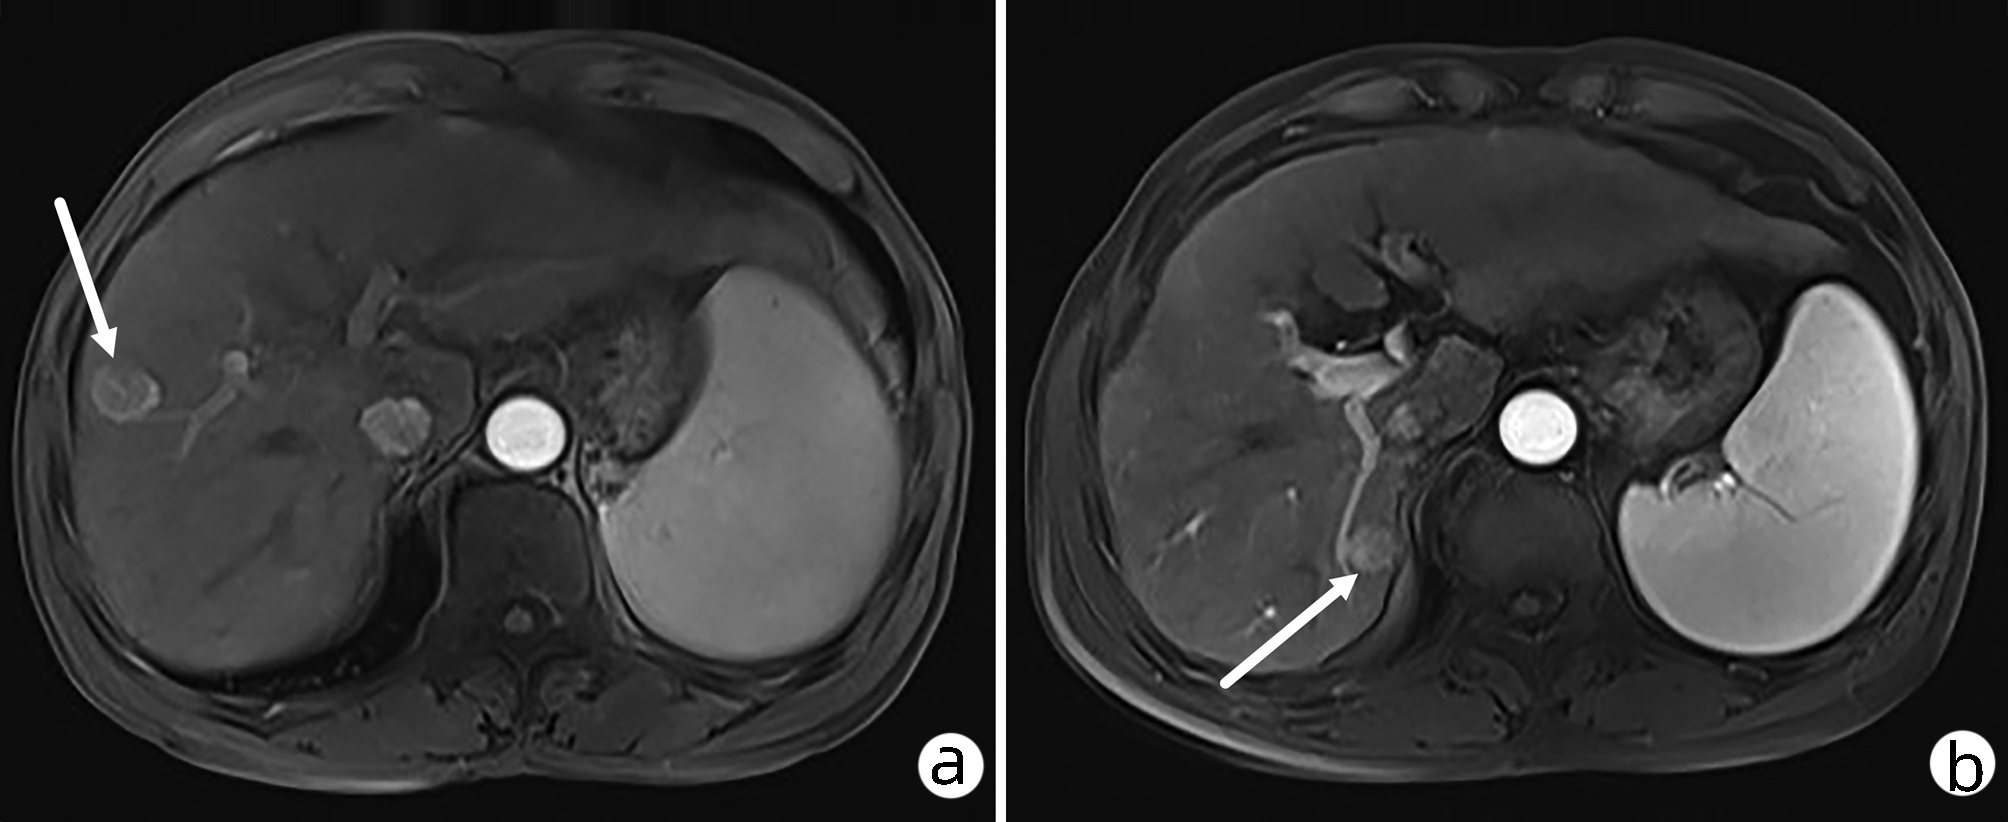

肝细胞癌微波消融术后迟发性膈疝1例报告

摘要(877) HTML (328) PDF (2572KB)(61)